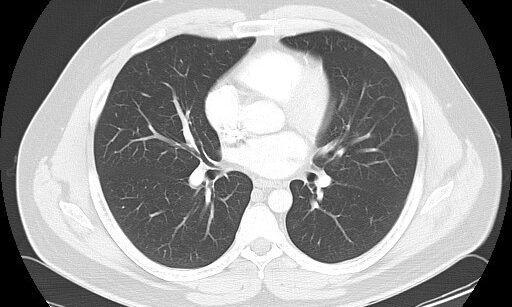

Your doctor may order a CT scan to confirm a suspected diagnosis or pinpoint the cause of symptoms. Doctors use CT scans to help visualize or determine the source of:

-Acute symptoms, such as shortness of breath or chest pain

-Blood clots or infections

CT angiography uses a CT scanner to produce detailed images of blood vessels and tissues throughout the body. An iodine-rich contrast material (dye) is usually injected through a small catheter placed in a vein of the arm. A CT scan is then performed while the contrast flows through the blood vessels to the various organs of the body. After scanning, the images will be processed using specialized software and a computer, and reviewed in different planes and projections.